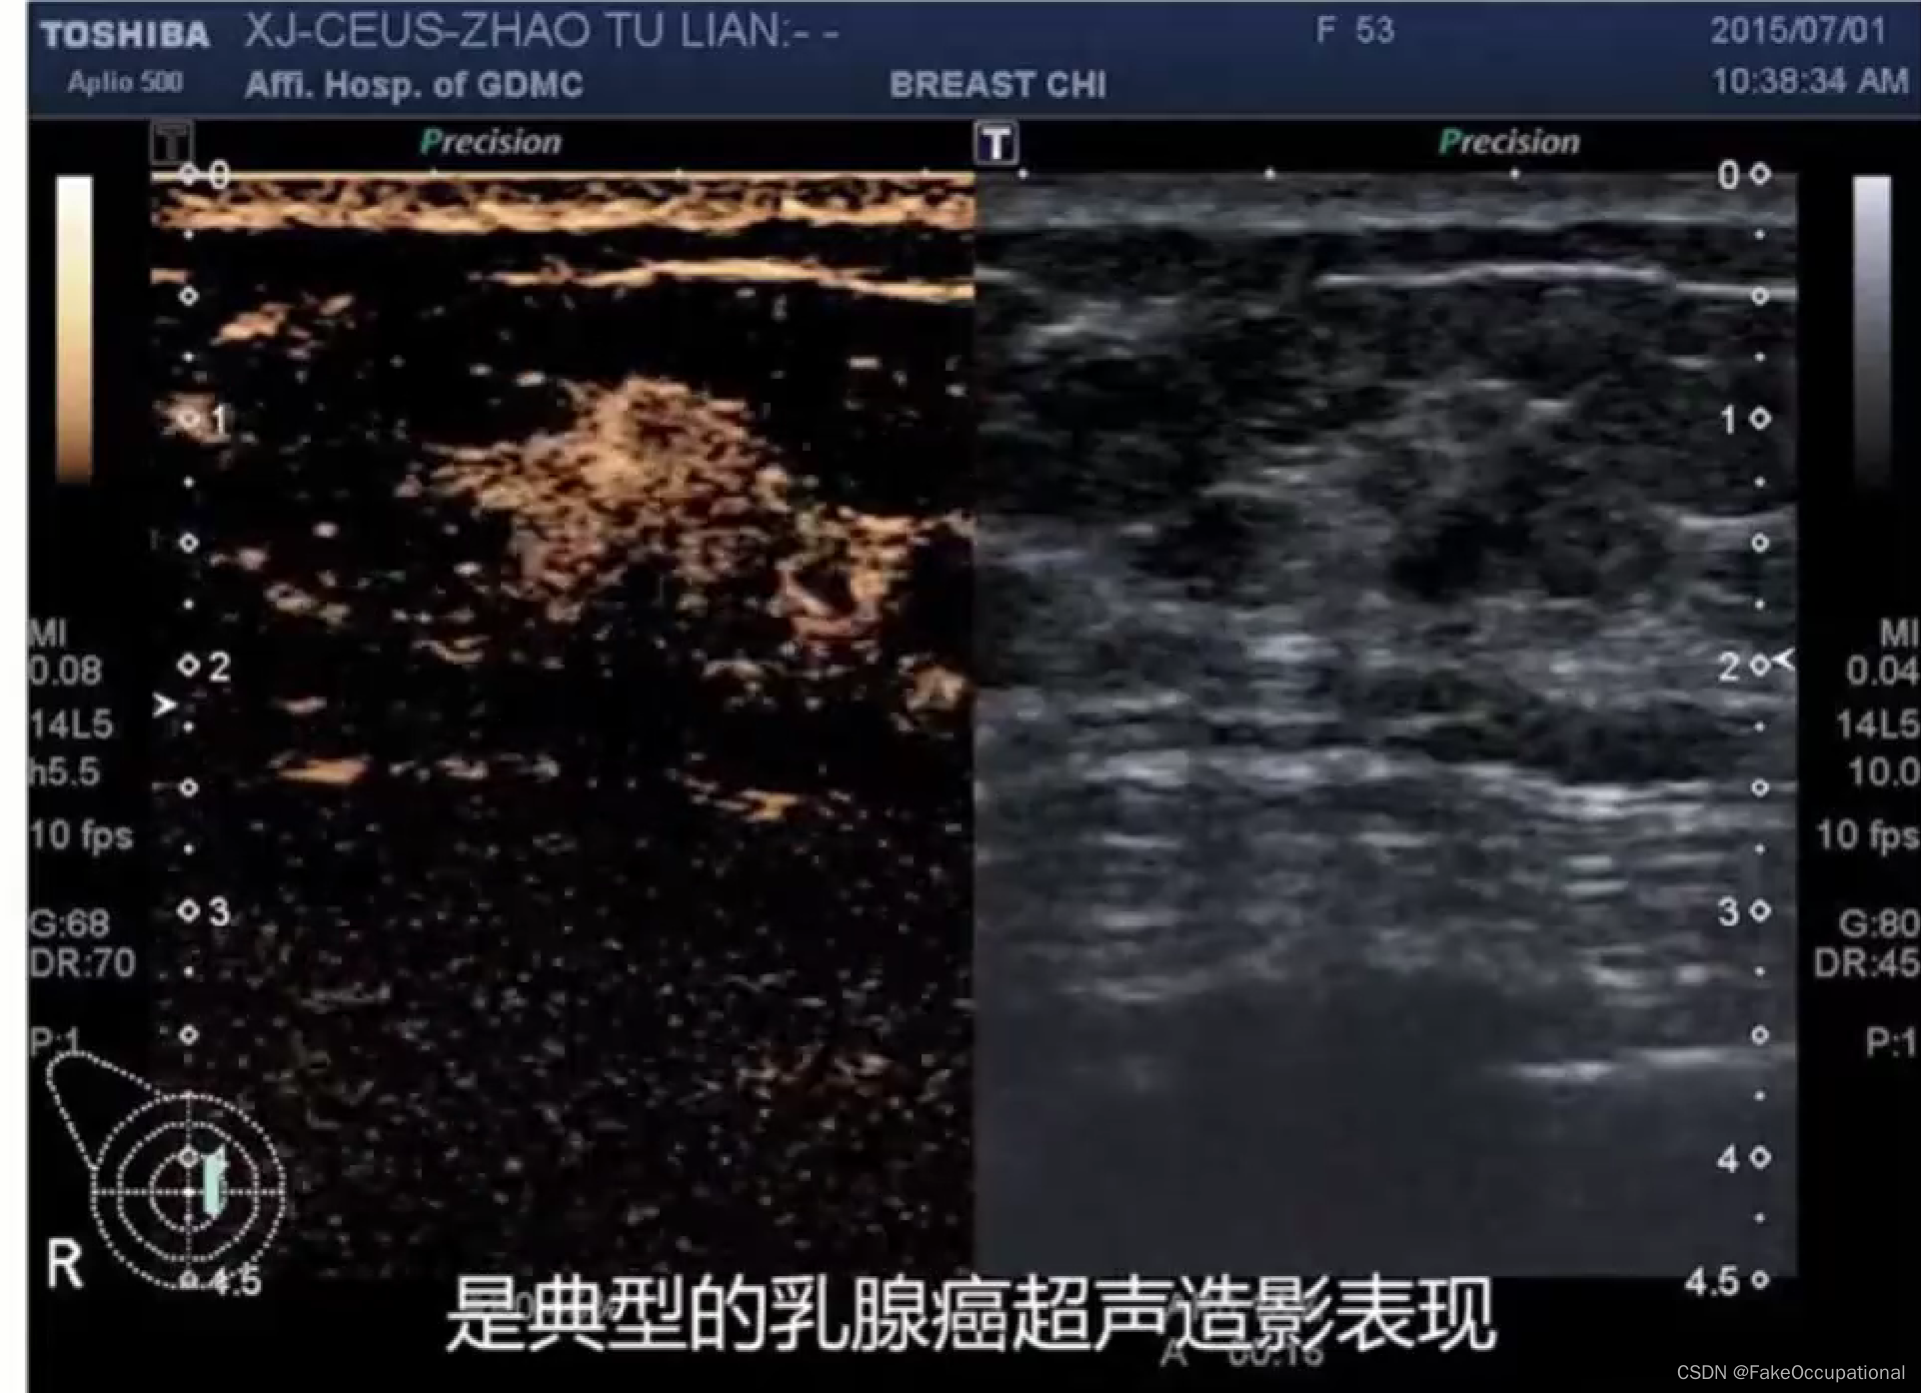

2.超声造影

乳腺癌

- 患者18岁,微小癌

- 其理论依据是恶性肿瘤常星离心性生长

- 淋巴结转移

乳腺超声进展

- 超声造影